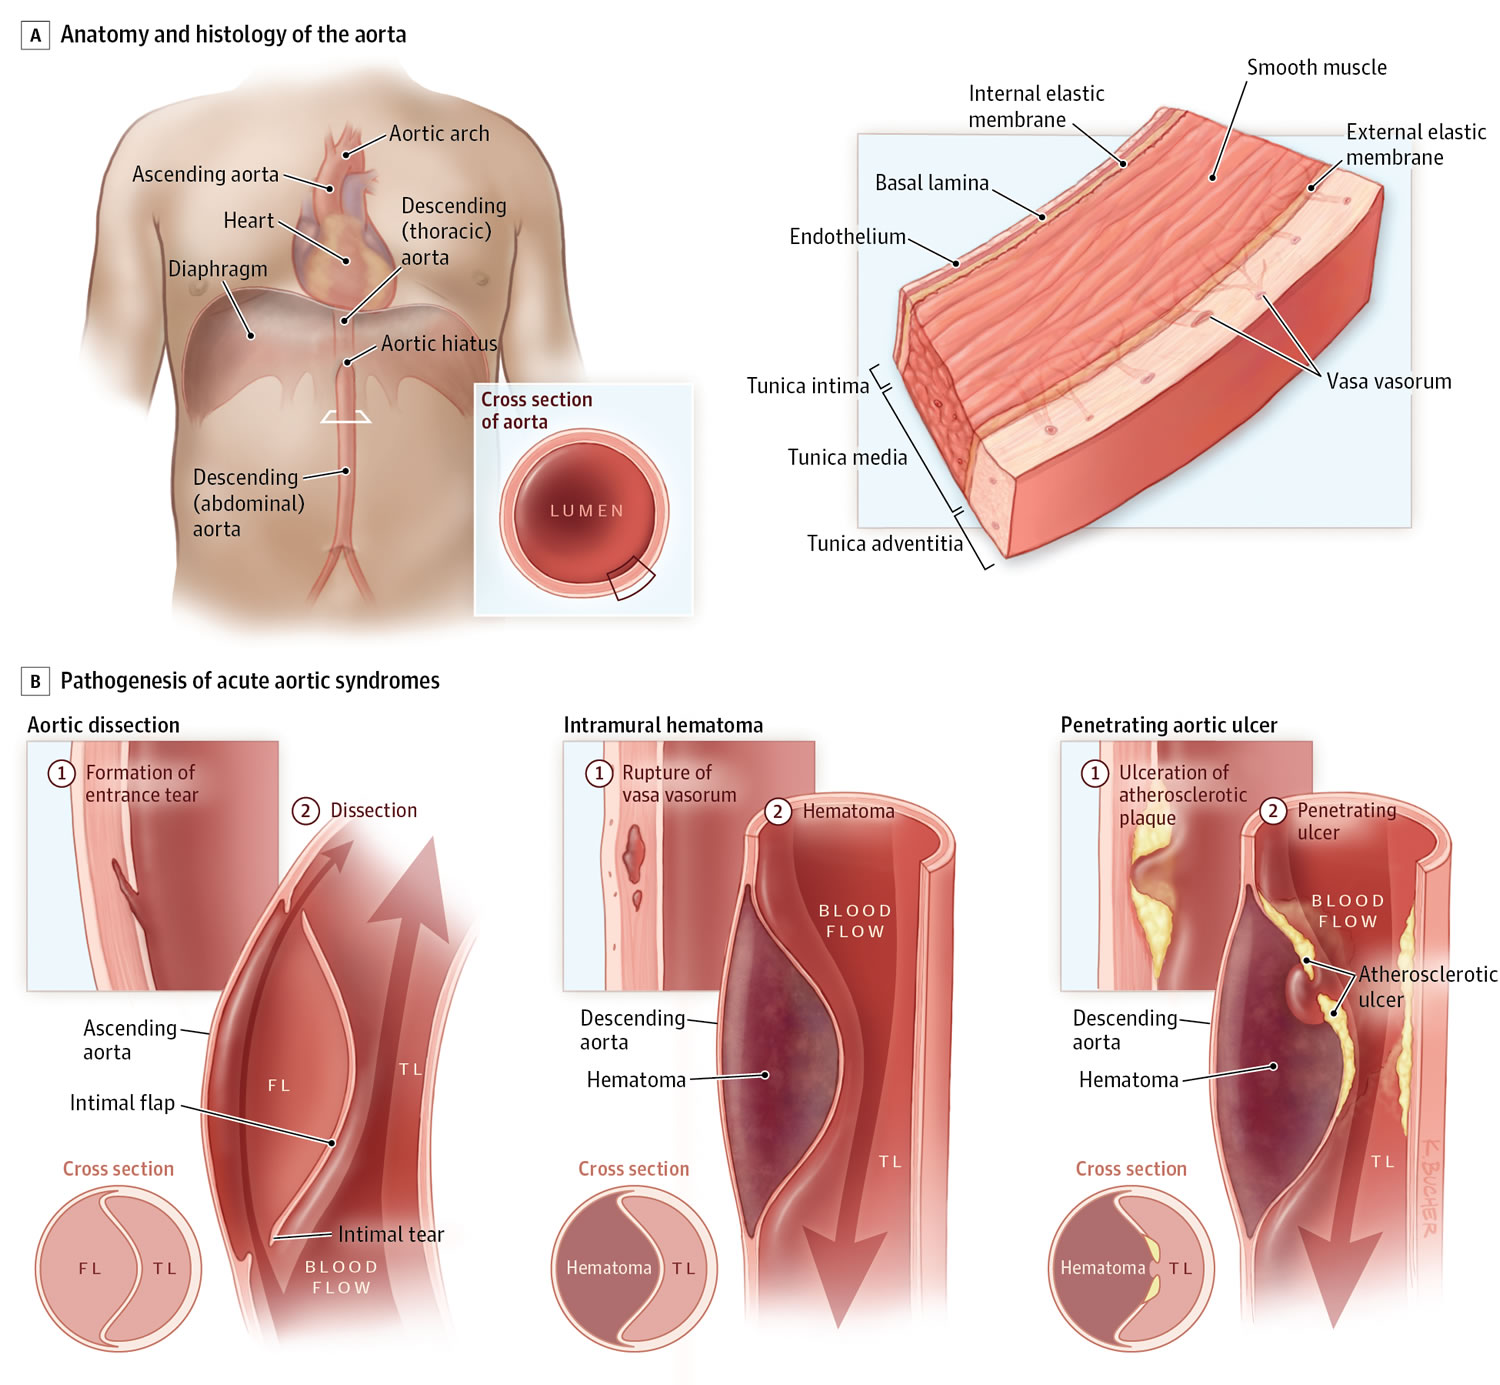

An Overview Of Aortic Dissection Edu svet gob gt

Figure 4 CTA Showing A Type A Aortic Dissection Extending Along The

Thoracic Aortic Dissection CT Radiology At St Vincent s University

Computed Tomography With Contrast Enhancement In A Patient With Acute